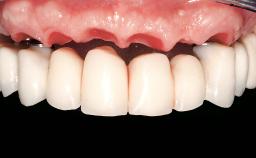

Immediate Loading of Eight Implants in the Maxilla and Six Implants in the Mandible and Final Restoration with Three-Unit and Four-Unit FDPs

German Gallucci, Jean-Pierre H Bernard, Urs C Belser

Extensive scientific evidence has confirmed that immediately loaded implants with fixed full-arch provisional restorations can osseointegrate with success rates similar to conventionally or delayed loaded implants. A number of immediate-provisionalization techniques for edentulous jaws have been described. Some protocols differ when it comes to prefabricated provisional templates versus complete denture conversion; intrasurgical impressions versus direct relining; and cemented versus screw-retained provisional restorations. In this context, complete-denture conversion has been proposed for either intrasurgical impressions or direct relining. Another possibility is the utilization of a prefabricated provisional to be adapted either in the mouth (by direct relining) or in the laboratory (on a working model obtained from an intrasurgical impression).